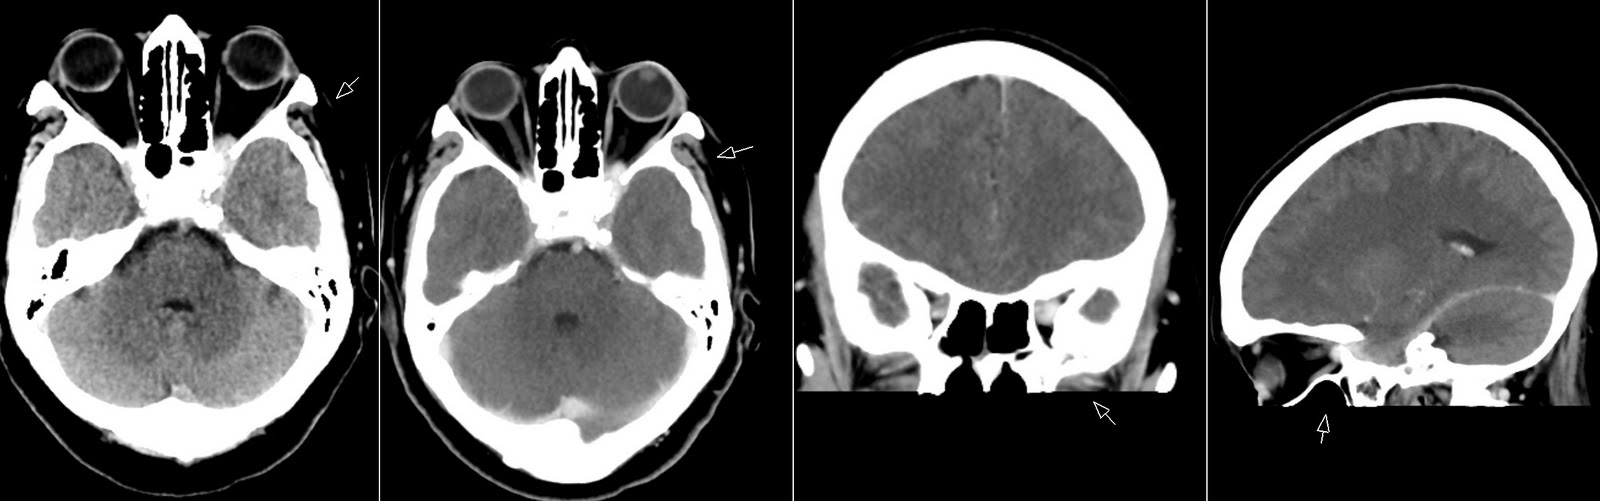

Синдром ханта симптомы 117 фото